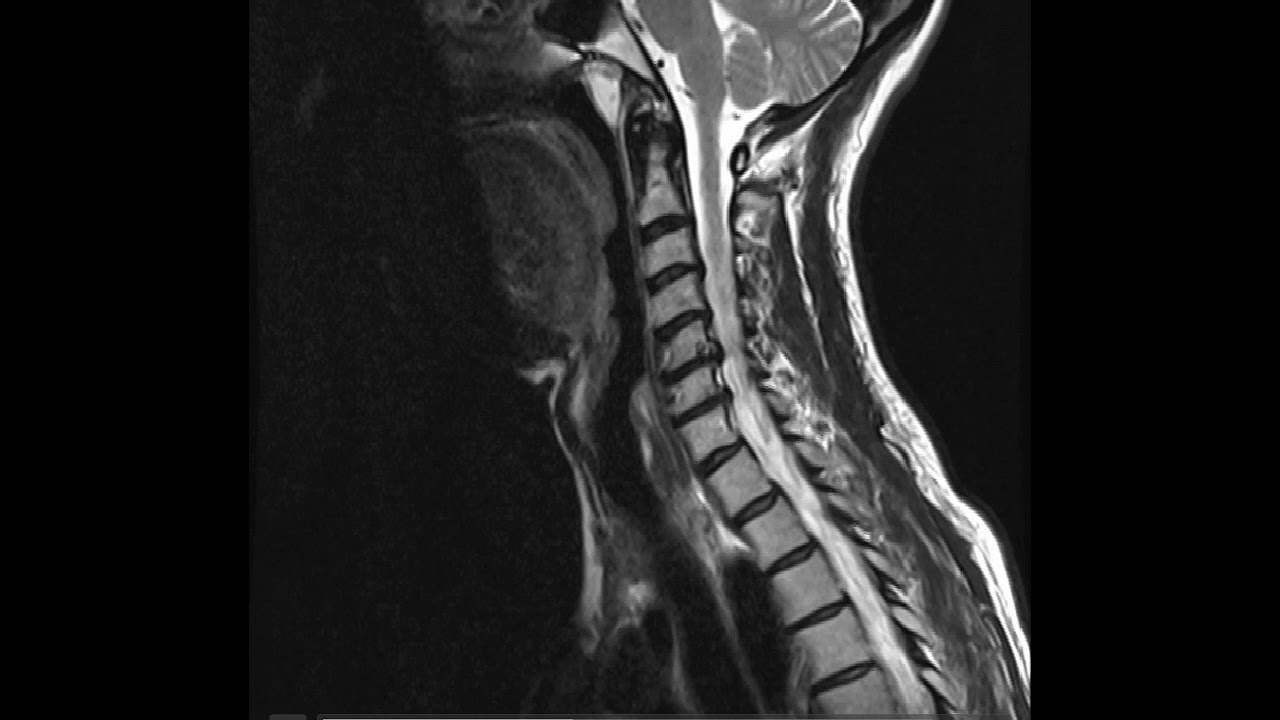

Último Resonancia Magnética Cervical (T2), corte sagital. Hiperintensidad de

WebLa Rm de la columna cervical está indicada en pacientes con dolor cervical con o sin traumatismo, sospecha de hernia discal, la planificación de cirugía y posterior. WebA menudo, las pruebas no son necesarias porque la mayoría de los dolores cervicales están causados por espasmos musculares y esguinces, que el médico diagnostica. WebLa principal ventaja de las imágenes de resonancia magnética antes de los métodos de radiación es una visualización clara de las fibras nerviosas, que permite. WebLa región cervical consta de siete secciones, o de vértebras, etiquetado como el atlas, el eje, y C-3, C-4, C-5, C-6 y C-7. Básico de los conocimientos anatómicos, es. WebLa resonancia magnética también se conoce como resonancia magnética nuclear (RMN) y tomografía por resonancia magnética (MRT). Una resonancia magnética cervical con. WebLa Resonancia de Columna Cervical permite detectar una variedad de afecciones de la columna cervical y problemas en los tejidos blandos de la columna vertebral,.

WebLa resonancia magnética de la columna cervical es un estudio preciso y seguro. Además, permite diagnosticar problemas neurológicos y esqueléticos. En. WebUna resonancia magnética de la columna cervical puede ayudar a evaluar varios síntomas y a diagnosticar tumores, hemorragias, infecciones o inflamaciones en las. WebLa resonancia magnética (o MRI) es un tipo de imaginería médica seguro y no invasivo que utiliza ondas de radio y un campo magnético para producir imágenes.